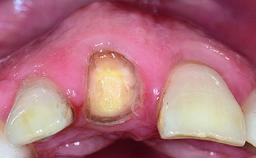

Replacement of a Missing Upper Left Central Incisor: Late Placement of an RC Bone Level Implant, CAD/CAM Zirconia Abutment

A healthy 37-year-old female patient was referred for a consultation on the replacement of missing tooth 21 with an implant-supported restoration. She stated that several years previously the tooth had been traumatically avulsed following a motor vehicle accident. The tooth was replaced with a three-unit fixed partial denture (FPD) immediately afterwards. Over time, she became disillusioned with the FPD and looked for a different option, including orthodontic therapy. She presented still in her orthodontic appliances, with the pontic sectioned free from the FPD but attached to the archwire. Her orthodontist felt that orthodontic treatment had been successfully completed, but nevertheless referred her before removing the appliances in case adjustments were necessary.

Soft Tissue Contour and Volume Slightly compromised